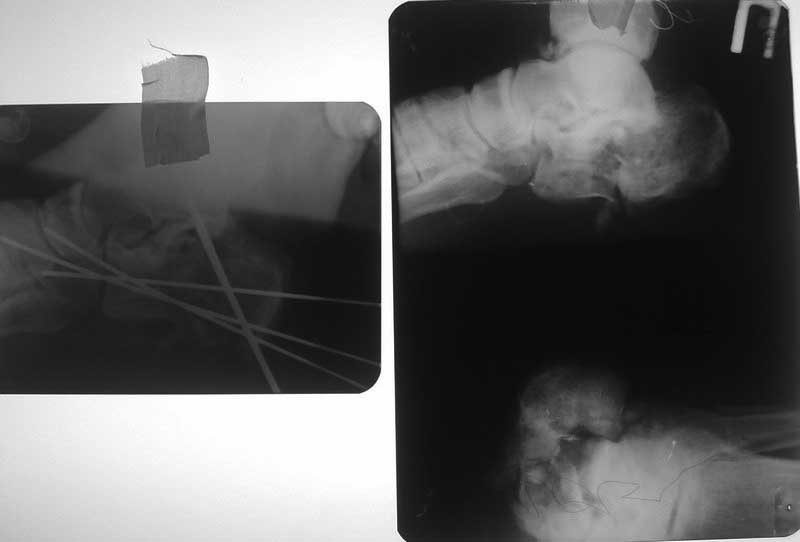

Пациент П. 40 лет пострадал в результате ДТП 30 07 12, в ургентном порядке ПХО (рана ушита?!),

гипсовая иммобилизация. К нам в клинику переведен 3 08 12 с диагнозом: Открытый 3ст.

оскольчатый перелом правой пяточной кости со смещением, перелом м.берцовой кости в н/3,

повреждение a.tibialis post. Проведена ХО, репозиция перелома, фиксация спицами, 4 08 12